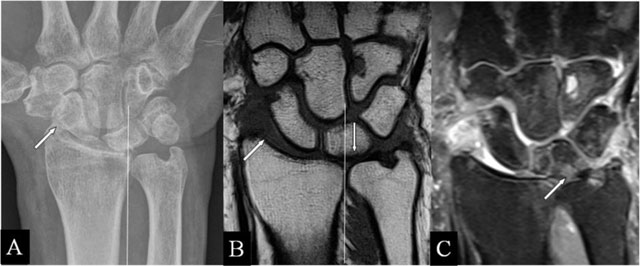

Figure 5

Ulnar translation with abutment. (A) PA plain radiograph; (B) Coronal SE T1-WI; and (C) Coronal SE PD-WI FS. (A–C) Lateral widening of the radioscaphoid joint (oblique arrow) and the lunate bone overlapping less than 50% with the corresponding radial articular fossa due to the ulnar translation of the carpus. (B, C) Cartilage destruction, oedema, and an accompanying lesion of the TFCC.